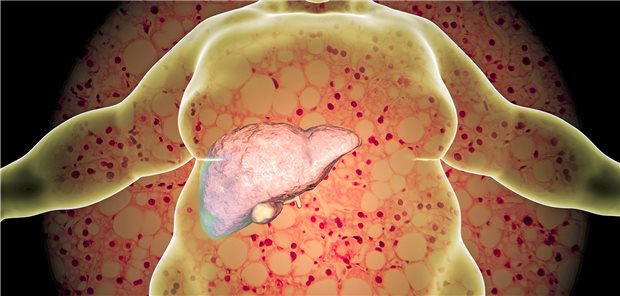

Zum internationalen Tag der nicht-alkoholischen Steatohepatitis am 10. Juni machen sich mehrere deutsche Fachgesellschaften für eine bessere Früherkennung und Vorsorge der Steatosis hepatis stark.

Drei von vier Diabetikern haben eine Fettleber und damit ein hohes Risiko für eine nicht-alkoholische Steatohepatitis (NASH). Darauf wird auch zum „Internationalen NASH-Tag“ am 10. Juni hingewiesen.